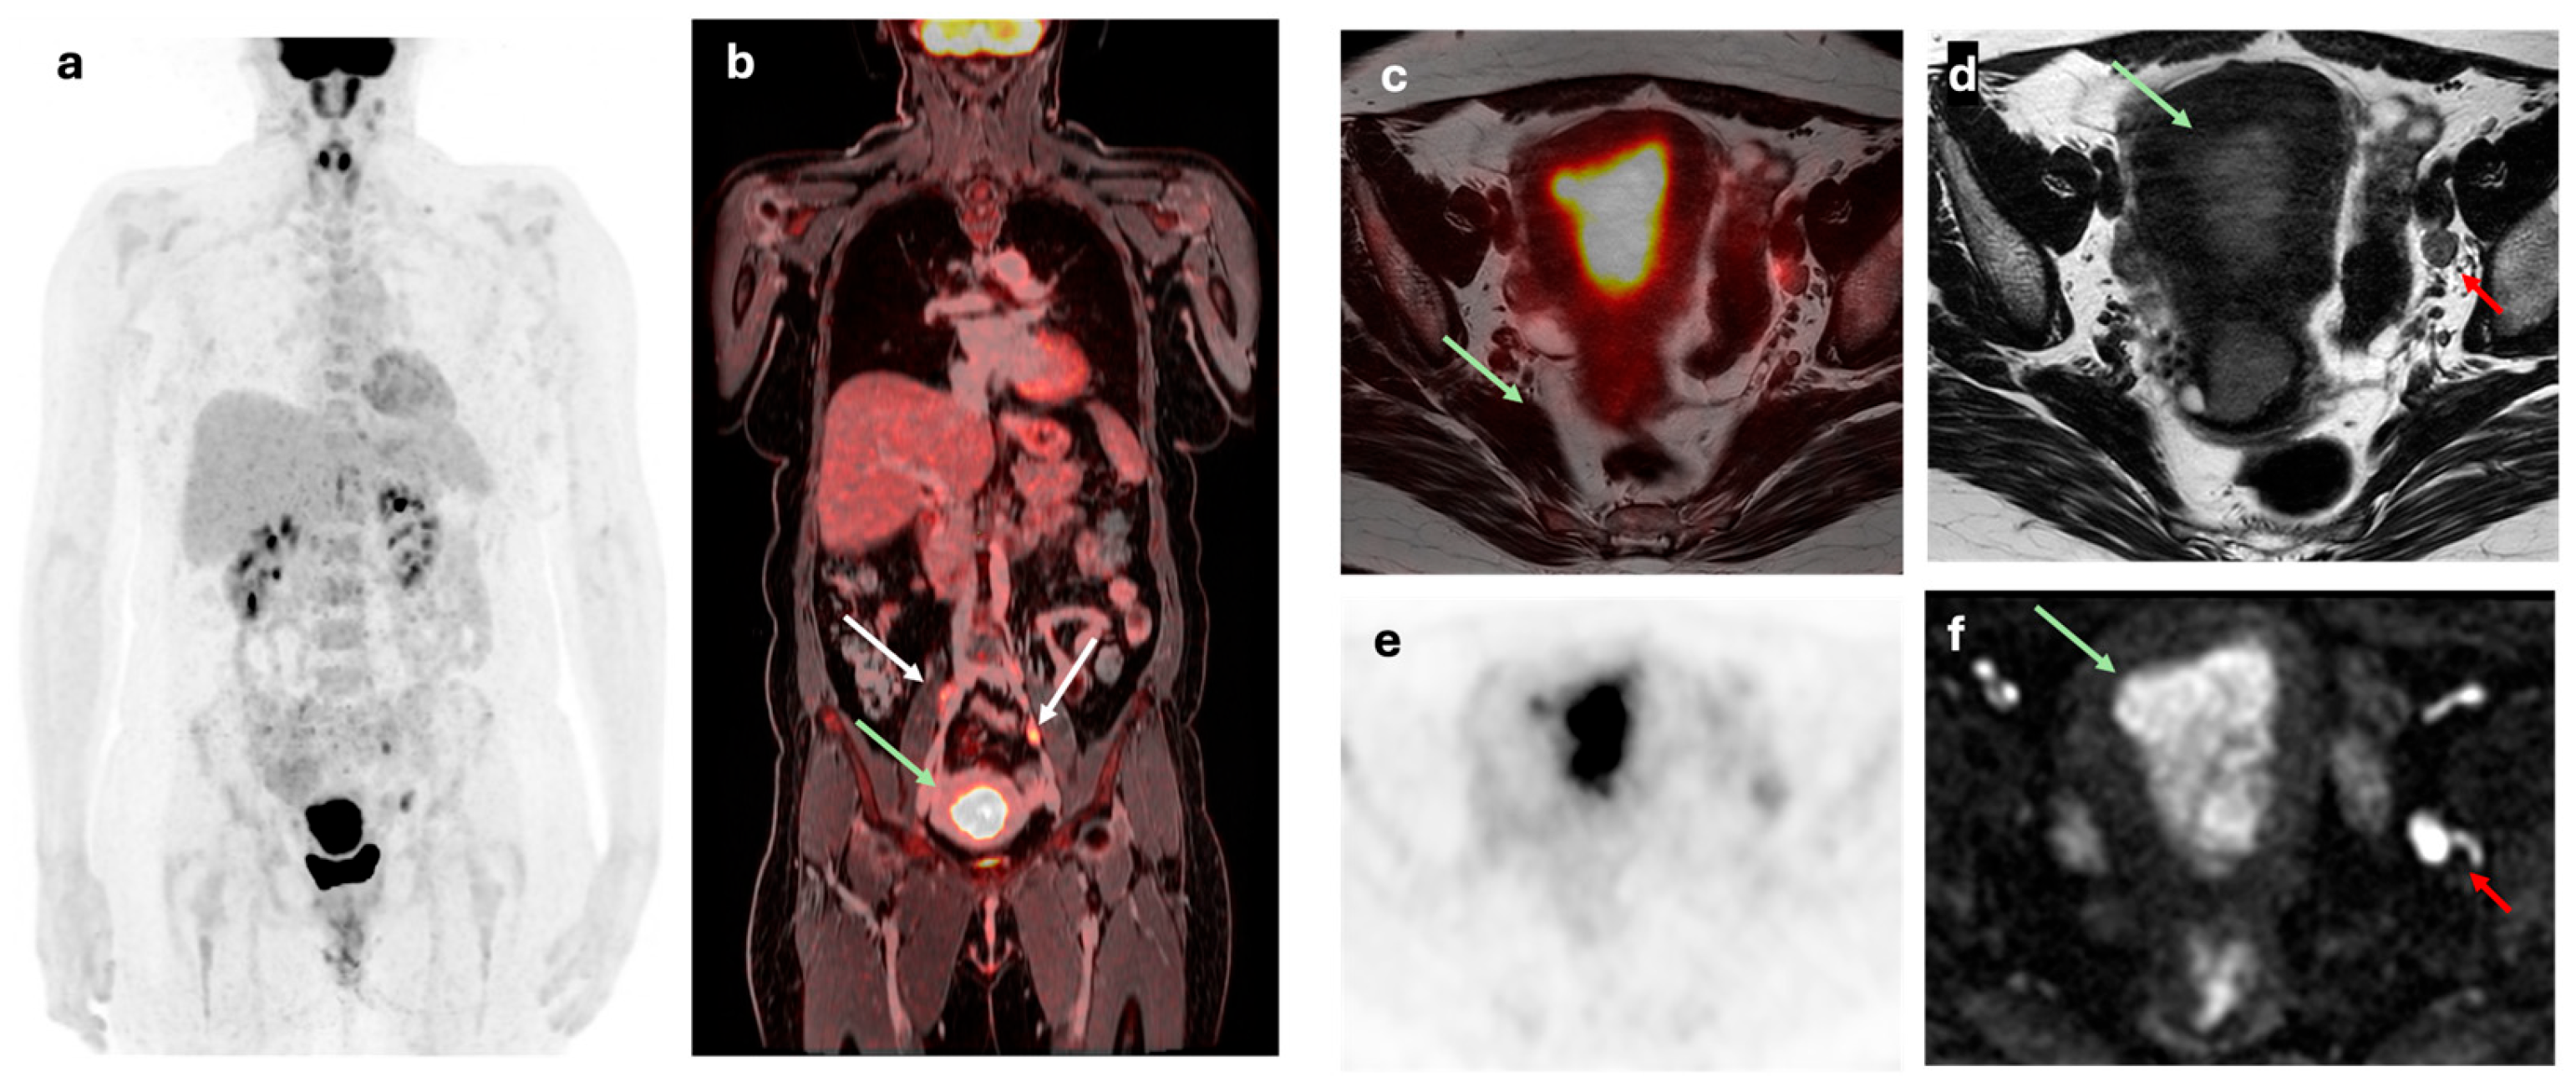

- Bian, L.; Wang, M.; Gong, J.; Liu, H.; Wang, N.; Wen, N.; Fan, W.; Xu, B.; Wang, M.; Ye, M.; et al. Comparison of Integrated PET/MRI with PET/CT in Evaluation of Endometrial Cancer: A Retrospective Analysis of 81 Cases. PeerJ 2019, 7, e7081. [CrossRef]

- Ironi, G.; Mapelli, P.; Bergamini, A.; Fallanca, F.; Candotti, G.; Gnasso, C.; Taccagni, G.L.; Sant’Angelo, M.; Scifo, P.; Bezzi, C.; et al. Hybrid PET/MRI in Staging Endometrial Cancer: Diagnostic and Predictive Value in a Prospective Cohort. Clin Nucl Med 2022, 47, e221–e229. [CrossRef]

- Yu, Y.; Zhang, L.; Sultana, B.; Wang, B.; Sun, H. Diagnostic Value of Integrated 18F-FDG PET/MRI for Staging of Endometrial Carcinoma: Comparison with PET/CT. BMC Cancer 2022, 22, 947. [CrossRef]

- Kitajima, K.; Suenaga, Y.; Ueno, Y.; Kanda, T.; Maeda, T.; Takahashi, S.; Ebina, Y.; Miyahara, Y.; Yamada, H.; Sugimura, K. Value of Fusion of PET and MRI for Staging of Endometrial Cancer: Comparison with 18F-FDG Contrast-Enhanced PET/CT and Dynamic Contrast-Enhanced Pelvic MRI. Eur J Radiol 2013, 82, 1672–1676. [CrossRef]

- Bezzi, C.; Zambella, E.; Ghezzo, S.; Fallanca, F.; Samanes Gajate, A.M.; Franchini, A.; Ironi, G.; Bergamini, A.; Monaco, L.; Evangelista, L.; et al. 18F-FDG PET/MRI in Endometrial Cancer: Systematic Review and Meta-Analysis. Clin Transl Imaging 2022, 10, 45–58. [CrossRef]

- Weissinger, M.; Bala, L.; Brucker, S.Y.; Kommoss, S.; Hoffmann, S.; Seith, F.; Nikolaou, K.; la Fougère, C.; Walter, C.B.; Dittmann, H. Additional Value of FDG-PET/MRI Complementary to Sentinel Lymphonodectomy for Minimal Invasive Lymph Node Staging in Patients with Endometrial Cancer: A Prospective Study. Diagnostics (Basel) 2024, 14, 376. [CrossRef]

- Tsuyoshi, H.; Tsujikawa, T.; Yamada, S.; Okazawa, H.; Yoshida, Y. Diagnostic Value of 18F-FDG PET/MRI for Staging in Patients with Endometrial Cancer. Cancer Imaging 2020, 20, 75. [CrossRef]